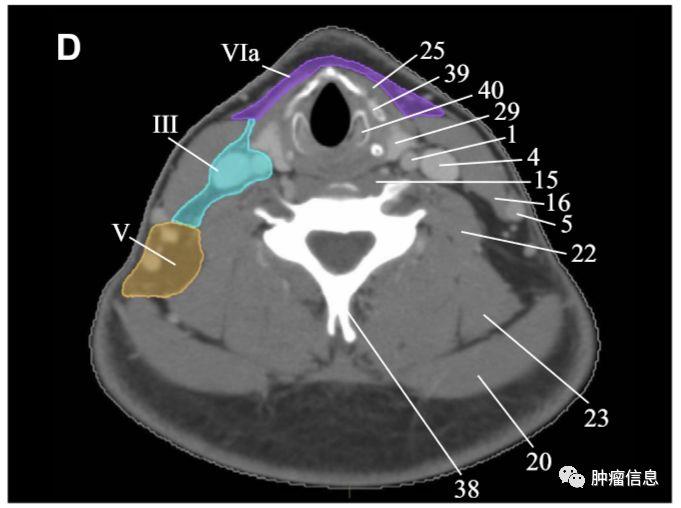

颈部III区淋巴结

上界:舌骨上缘下界:环状软骨下缘前界:胸骨舌骨肌侧后缘后界:胸锁乳突肌后缘内界:颈血管鞘内缘、头长肌外侧界:胸锁乳突肌内缘

颈部III区图中绿色为III区

颈部V区淋巴结

上界:颅底下界:锁骨上缘前界:胸锁乳突肌后缘后界:斜方肌前缘VA:环状软骨下缘以上区域VB:环状软骨下缘至锁骨上缘区域

颈部V区图中黄色为V区

颈部VI区淋巴结

颈前淋巴结上界:舌骨下界:胸骨切迹后界:颈动脉鞘前方

颈部VI区图中紫色区域为VI区(VIa、VIb)

RTOG2013年头颈部淋巴结分区勾画图谱:

Ia:颏下淋巴组Ib:颌下淋巴组II:上颈淋巴组III :中颈淋巴组IVa:下颈淋巴组IVb:锁骨上内侧组V:颈后三角淋巴组Va:上颈后三角淋巴组Vb:下颈后三角淋巴组Vc:锁骨上外侧组VI:颈前淋巴组VIa:颈前淋巴结VIb:喉前、气管前、气管旁淋巴结VII:椎前淋巴组VIIa:咽后淋巴结VIIb:茎突后淋巴结VIII:腮腺淋巴组IX:面颊淋巴组X:颅底后组Xa:耳后、耳下淋巴结Xb:枕淋巴结见下图: